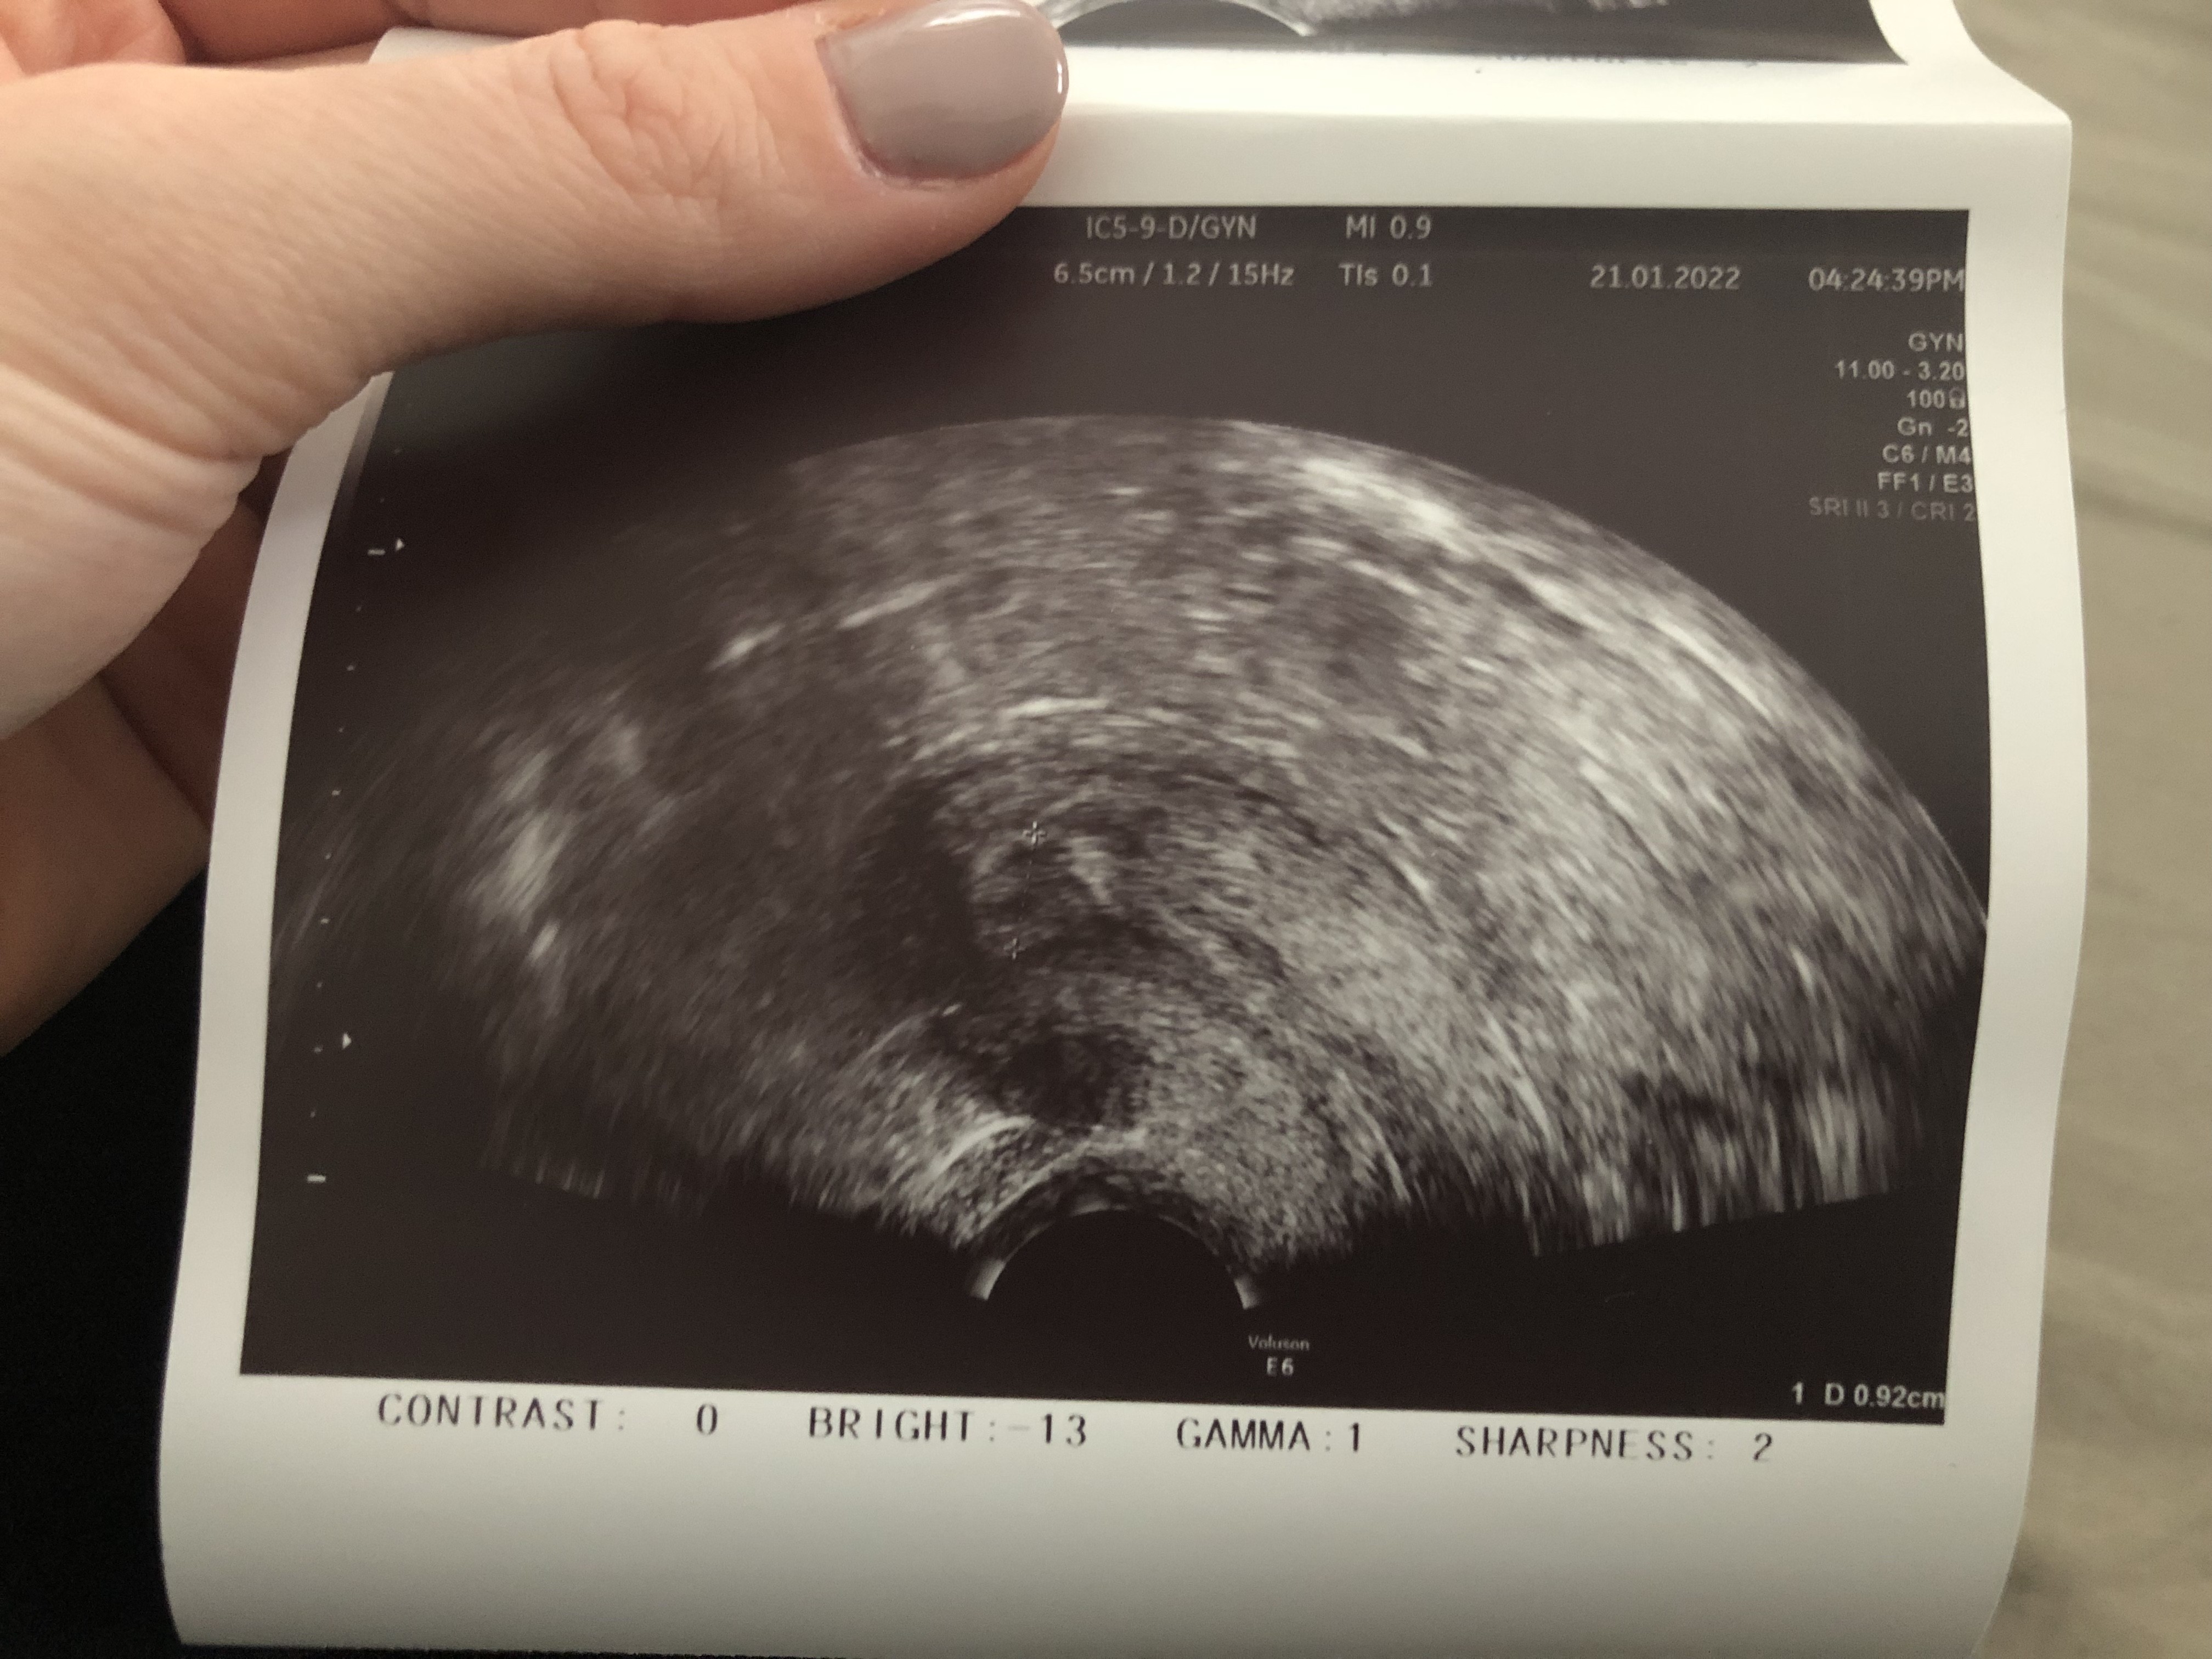

W którym miejscu na zdjęciu będzie to endometrium? To będzie to ze zdjęcia 0,75? Takie miałam w 14dc w 15 owu a w 16 0,92 jeśli dobrze odczytuje.A co masz na opisie? Powinnaś mieć grubość endometrium, wielkość jajników i wielkość pęcherzyków dominujących przynajmniej w 2 wymiarach.

A pokaż całość zdjęcia z tym wymiarem 0,75 bo ucięłaś połowę. To może być oczywiście endometrium.W którym miejscu na zdjęciu będzie to endometrium? To będzie to ze zdjęcia 0,75? Takie miałam w 14dc w 15 owu a w 16 0,92 jeśli dobrze odczytuje.

Wrzucam akurat z dnia po owu 0,92 jest o ile coś widaćA pokaż całość zdjęcia z tym wymiarem 0,75 bo ucięłaś połowę. To może być oczywiście endometrium.

Szczerze Ci powiem pierwszy raz widzę taki obraz endometrium, więc nie mam bladego pojęcia czy to to. Ale z drugiej strony nie jest to ani jajnik ani nic innego. Szkoda że nie dostałaś opisuWrzucam akurat z dnia po owu 0,92 jest o ile coś widać![]()